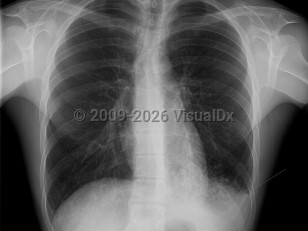

SarcoidosisSarcoidosis